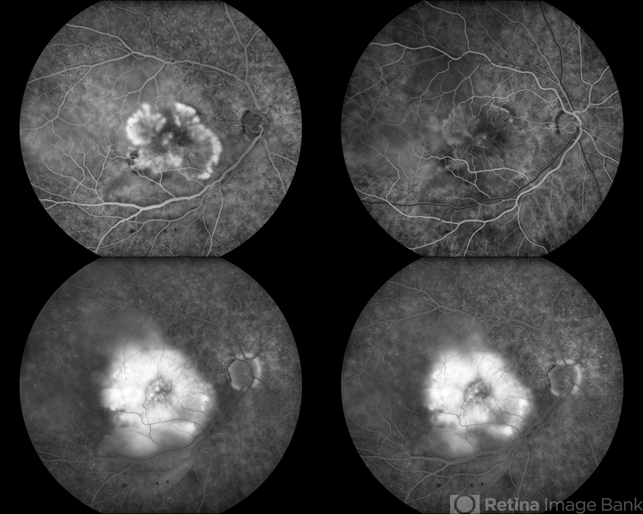

- choroidal neovascularization (CNV), age-related macular degeneration (AMD)

- Patient complains of gray spot in vision in the right eye. Fluorescein angiogram shows abnormal blood vessels leaking. Patient was treated with eylea Injection and will return for follow up in 1 month.